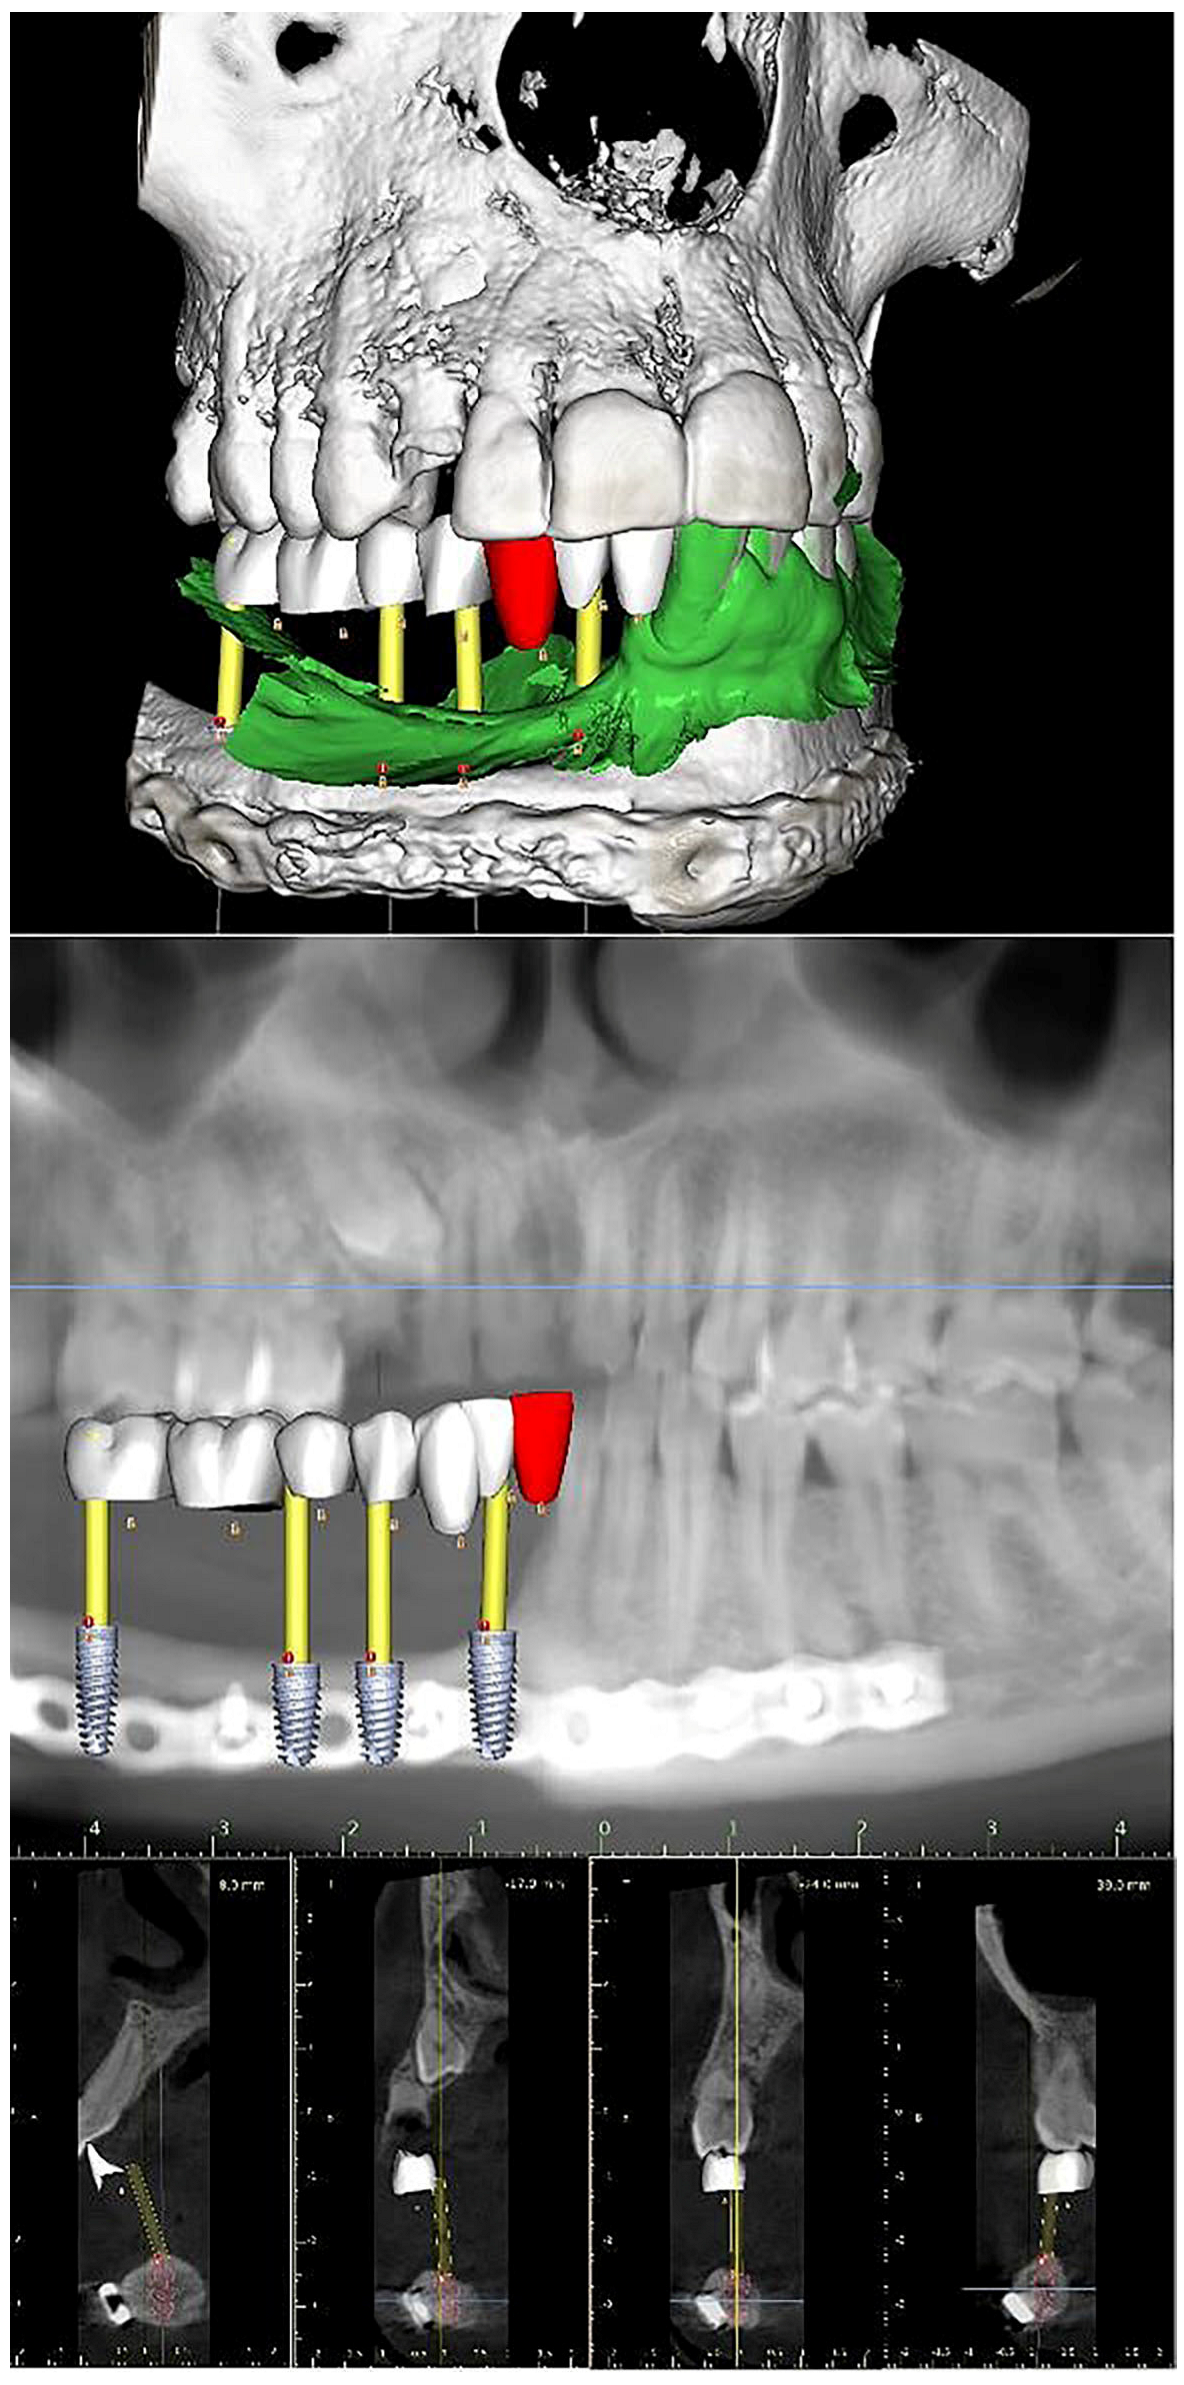

| 2022–2023 | Complementary exams and planification |

| 2023 | Surgery of 4 implants in the jaw |